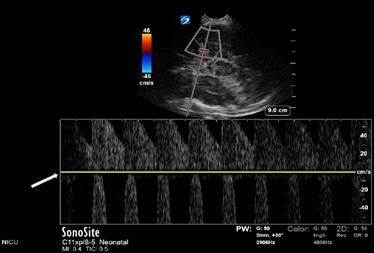

Neonatology Normal Anatomy Aliasing Image